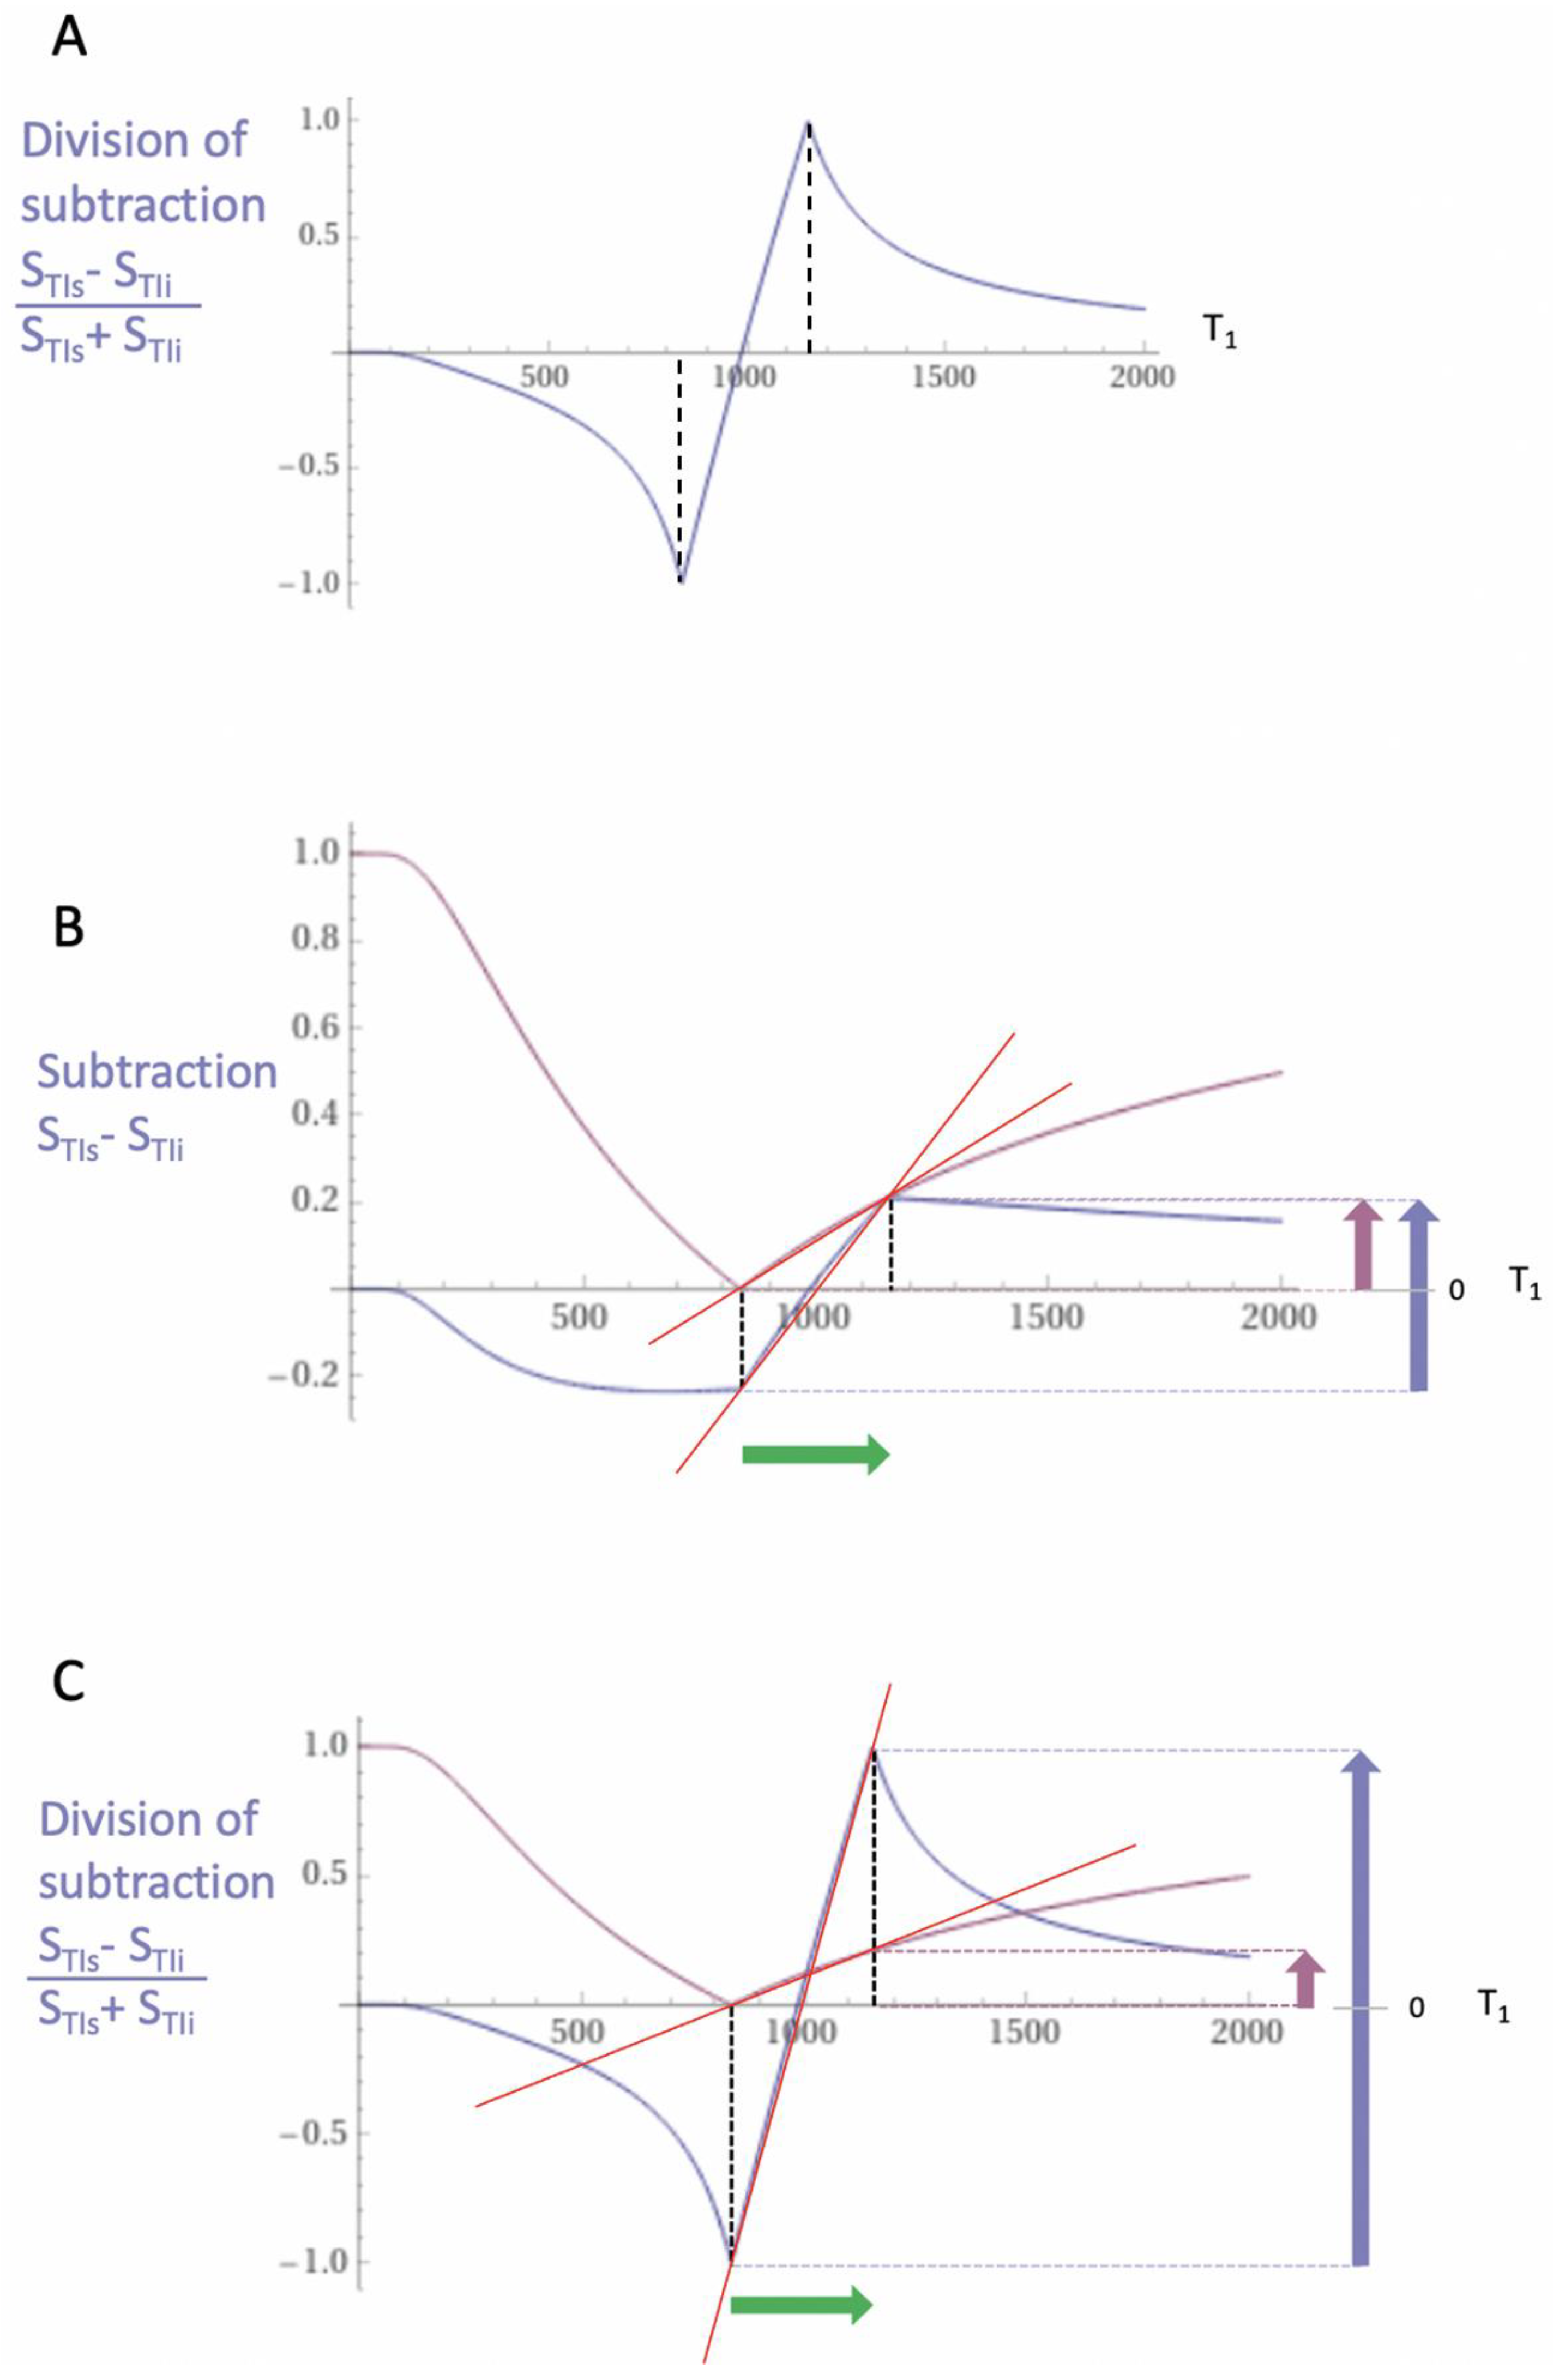

2. Basic Physics

2.1. Tissue Property Filters (TP-Filters) and the Inversion Recovery (IR) Sequence

| 4 | dSIR | Figure 2 and Figure 3 | |

| 7 | dSIR, SdSIR | (in mD) | Figure 2 |

| 8 | dSIR, T1 | (in mD) | Figure 2 |